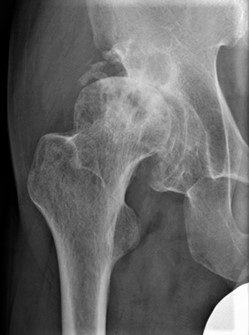

股関節の軟骨がすり減ることで痛みが生じる病気で圧倒的に女性に多いのが特徴です。骨の形の異常から二次的に発症するものが9割で、幼少期の股関節発育不全(臼蓋形成不全)のために骨盤側の受け皿の部分が浅いことが原因です。

〈変形性股関節症〉

関節の隙間が消失